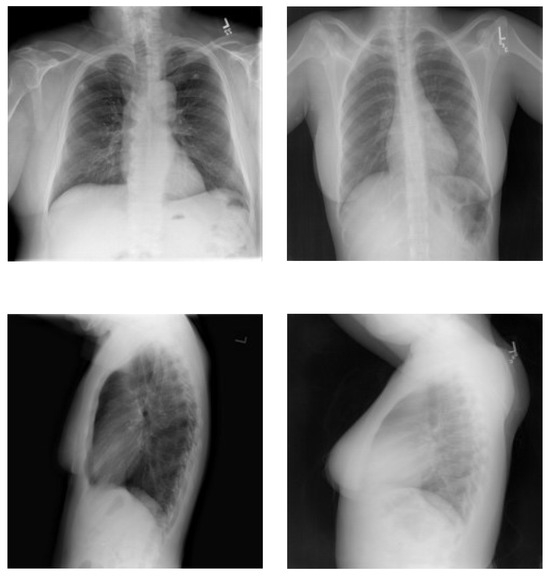

2.1. Turkish Chest X-Ray Images Medical Report Generation Dataset